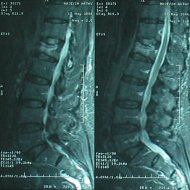

Kemik erimesine (osteoporoza) bağlı omurga kırığı olan hastada vertebroplasti (çimento ile dolgu) tedavisi